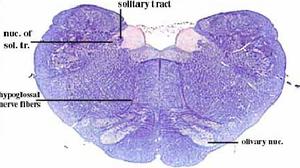

secciones transversales a diferentes niveles del tronco del encéfalo mostrando la localización de los núcleos neuronales aferentes de los nervios craneales

AFERENTES:

Somatoaferentes:

generales (GSA): boca y cara

-especiales (SSA): sentido de la visión y oído

Visceroaferentes:

- generales (GVA): recogen sensación de faringe y laringe

-especiales (SVA): sentido del gusto y del olfato

correspondencias entre la localización de los núcleos neuronales en diferentes cortes.